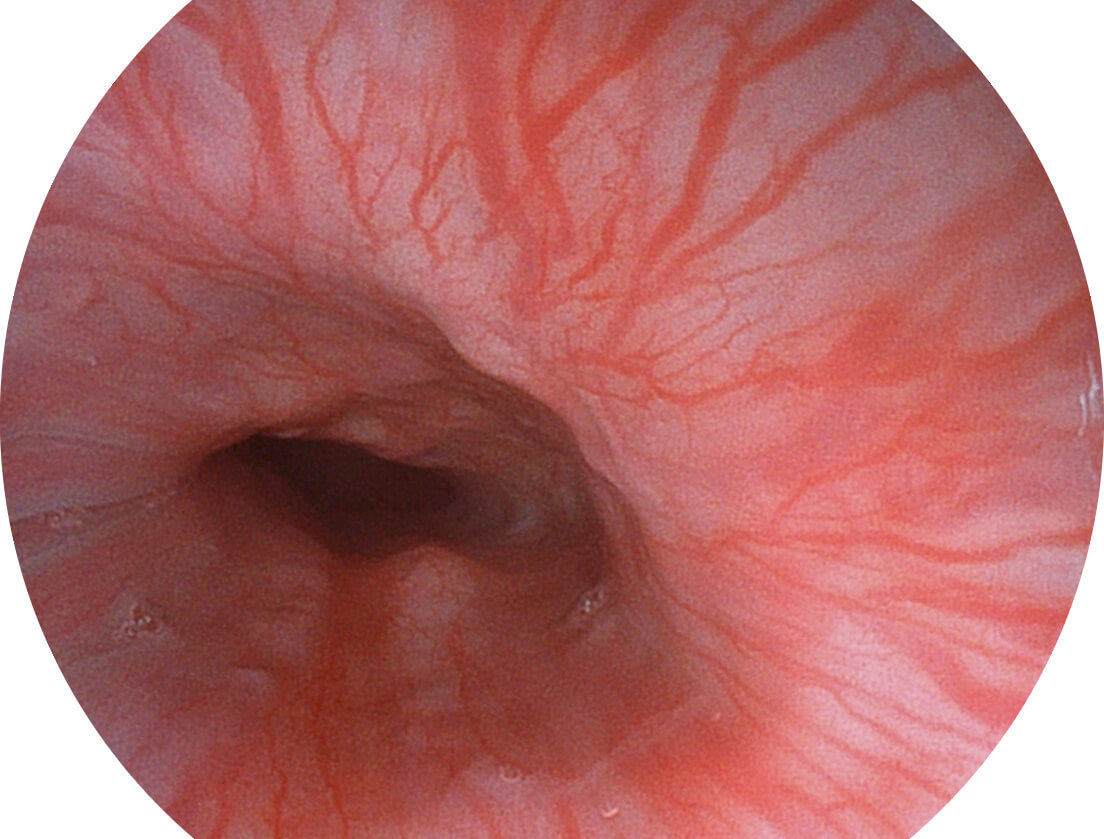

Versatile Intelligent Staining Technology, VIST

强调浅层黏膜结构的同时,保证照明亮度和提升浅层微血管与中层血管颜色对比度,病变边界更清晰。

白光图像